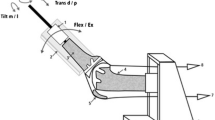

The specimens were mounted into a specially designed knee simulator in which isokinetic flexion–extension moments are simulated (Fig. 1). The knee specimens were oriented with the femur fixed horizontally and the patella facing downwards. The tibia was attached to the simulator at mid-length by means of a linear-rotational bearing which permits axial sliding and turning of the tibia. The bearing in turn was attached to a swing-arm, which allows varus–valgus rotation. The resulting arrangement gives complete freedom of motion of the joint, with the exception of flexion–extension, which is determined by the position of the swing arm. The swing arm was equipped with a strain gauge based load-measuring device which allows the torsional moment applied to the tibia to be monitored continuously. Movement of the tibia was generated by the coordinated activation of three hydraulic cylinders, one to simulate quadriceps muscle force, one to simulate a proprioreceptive co-contraction of the hamstring muscles and the third to apply an external flexion moment. A specially constructed tendon clamp, which allowed application of loads up to 2,000 N, was used to attach the quadriceps tendon and the hamstrings tendons to the hydraulic cylinder with a steel cable (Fig. 1).

The test cycle simulated an isokinetic extension cycle from 120° of flexion to full extension, the quadriceps cylinder thereby applied sufficient force to the quadriceps tendon in a closed-loop control cycle to produce a constant extension moment of 31 N m about the knee. During simulation, the force applied by this cylinder changed depending of flexion angle of the knee. The hamstring cylinder simulated the co-contraction of the hamstrings muscles with a constant co-contractive flexion force of the hamstrings of 200 N.